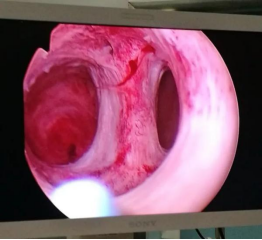

宫腔镜检查是诊断宫腔粘连的金标准,宫腔镜可以直接观察子宫内部情况,从而了解到粘连的具体情况,便于医生最终的确诊。

宫腔镜粘连分离术(TCRA)是目前子宫粘连患者通过手术治疗的首选方法。